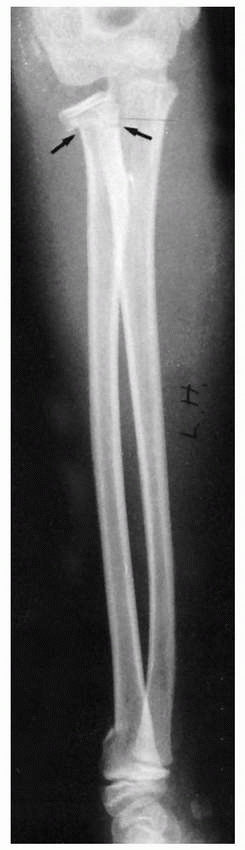

FIGURE 9-10 A.

Subperiosteal hemorrhage from an occult fracture of the distal radius causes an anterior displacement of the normal pronator quadratus fat pad (arrows). B. A 13-year-old girl with tenderness over the distal radius after a fall. The only radiographic finding is an anterior displacement of the normal pronator quadratus fat pad (arrow). C. The opposite normal side (arrow indicates normal fat pad). D. Two weeks later, there is a small area of periosteal new bone formation (arrow) anteriorly, substantiating that bony injury has occurred. |